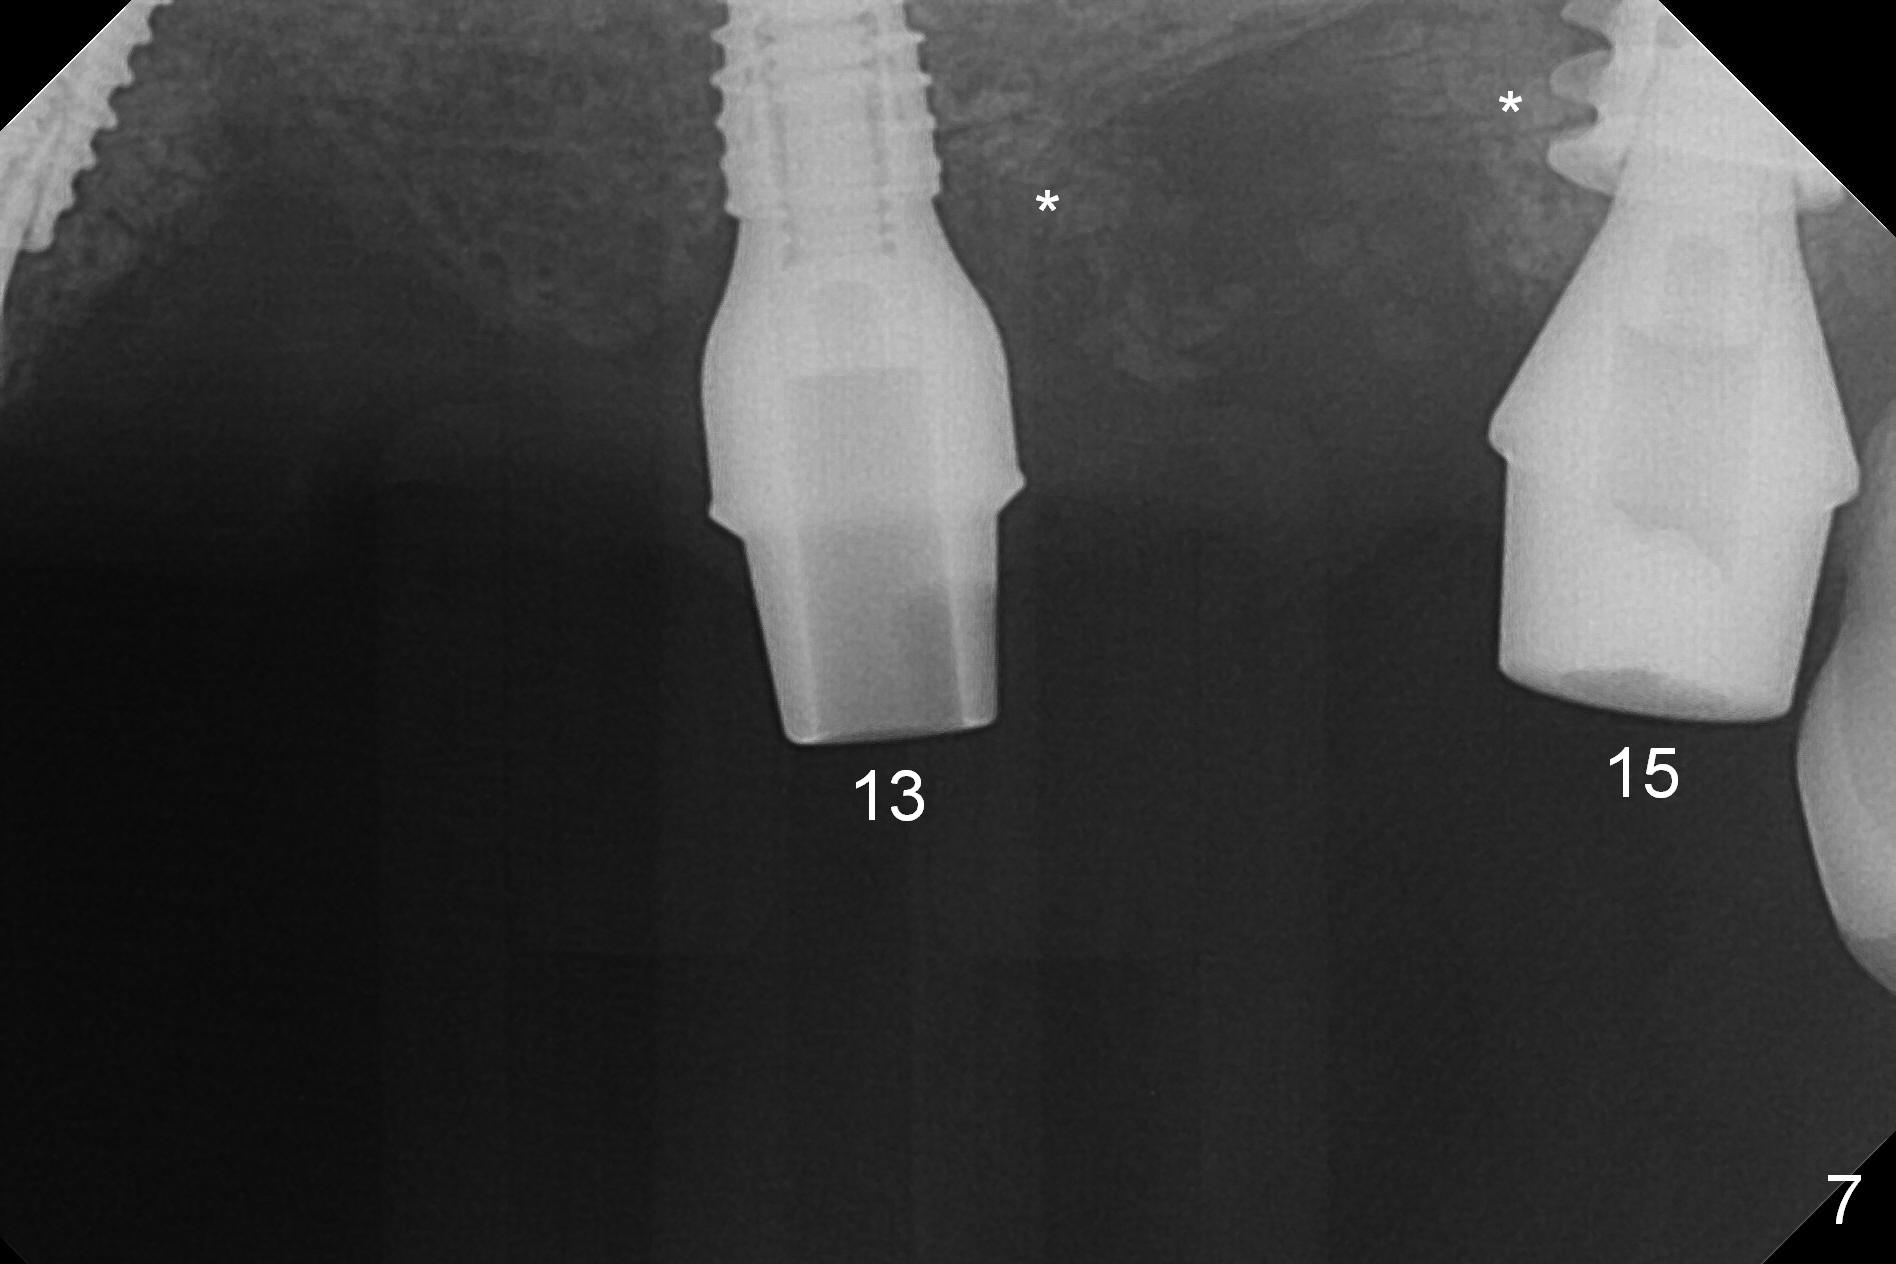

The posterior abutment of the 5-unit FPD, #15 is loose with the buccal roots extruded outside the sockets. The palatal socket is the appropriate site of immediate implant with the presence of the buccomesio-palatal walls, although short. The thinnest portion of the palatal socket is 1.6 mm (Fig.6 CBCT coronal section through the palatal root (P)). Magic Sinus Lifter cannot break through the sinus floor. UF drills are used to create osteotomy and sinus lift until 4.3 mm. A 5 mm tap drill is inserted without stability (Fig.1). A 5.5x9 mm IBS dummy implant achieves insertion torque of 10 Ncm, although it looks smaller (Fig.2) than the tap in Fig.1. After placement of PRF membrane and bone graft (allograft, autogenous bone and Osteogen, Fig.3 *), a 6x9 mm IBS implant is placed with insertion torque of 30 Ncm. It appears that the fins of the implant slice into the bone at high magnification for engagement. Following further placement of the implant, bone graft is packed into the distal portion of the socket (Fig.4 <). The thin fins extends into mesial and distal thicker bone (Fig.5 (CBCT sagittal view) *).

One month later, bone graft is placed mesiopalatal to the implant at #15 (Fig.7 *,8) while a 3.8x13 mm implant is placed at #13 following bone expansion (using Magic Split and Magic Expander 3.0 mm (abutment 5.5x4(5) mm). Another month later, the tooth #16 is extracted to create space for #15 restoration. Two weeks later the abutment at #15 is found to be unstable (2.5 months postop). Local oral hygiene is poor. The abutment is removed and a 6x4 mm healing abutment is placed with mild tenderness. It appears that the limited bone height is associated with low stability with CMC. Three months later (5.5 months postop), the implant seems to be stable (Fig.9,10). The implant remains stable clinically 7 months postop (Fig.11). The bone graft appears to mature and covers the abutment with provisional 24 months postop, the bony changes is related to the thick gingiva (Fig.12 ^).